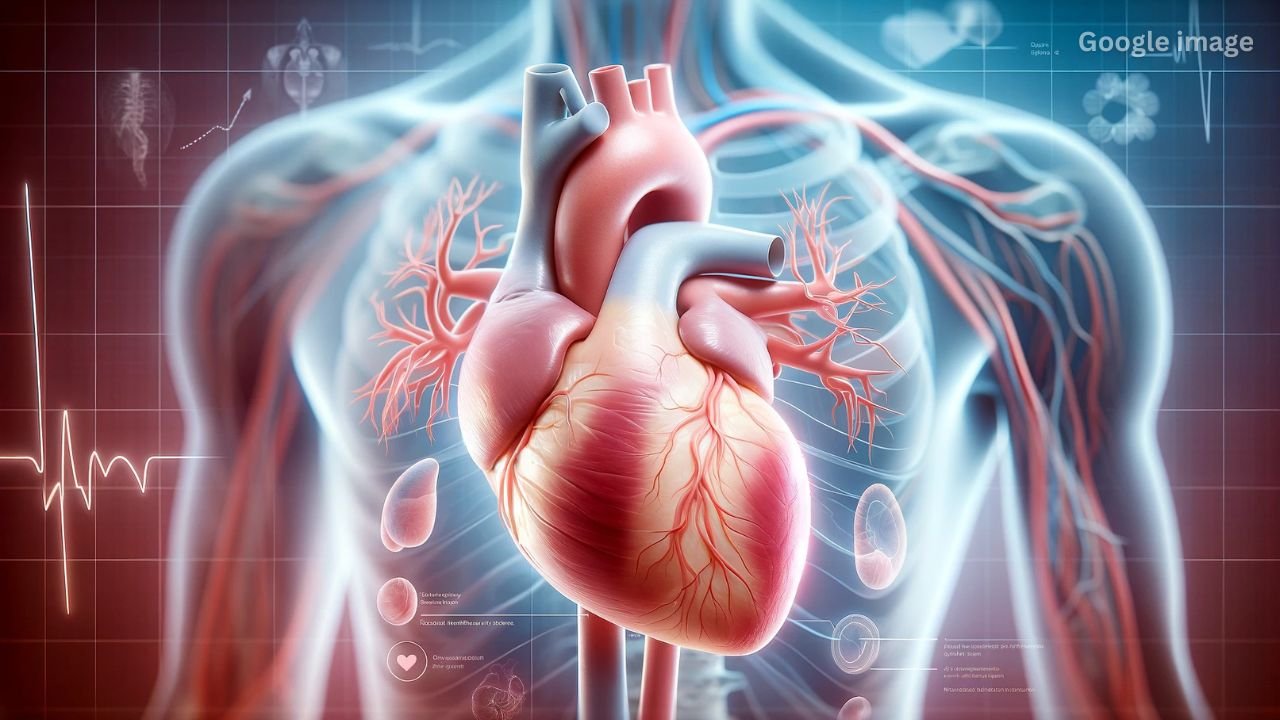

The rising incidence of serious and life-threatening heart diseases is a matter of concern. Not only a poor lifestyle but also an unhealthy diet can increase the risk of heart attack. Today, we’ll tell you about some foods and drinks that can negatively impact not only your heart health but also your overall health. Therefore, you should eliminate these foods from your diet as soon as possible or limit their consumption.